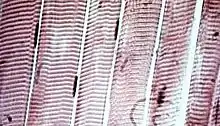

Skeletal muscle tissue is an elongated striated muscle tissue ranging from several millimeters to about 10 centimeters in length and from 10 to 100 micrometers in width.[3] Skeletal striated muscle tissue is arranged in regular, parallel bundles of myofibrils containing the many contractile units known as sarcomeres, which give the tissue its striated (striped) appearance. Skeletal muscle, is voluntary muscle anchored by tendons or sometimes by aponeuroses to bones, and is used to effect skeletal movement such as locomotion and to maintain posture. Postural control is generally maintained as an unconscious reflex, but the muscles responsible can also react to conscious control. An average adult man is made up of 42% of skeletal muscle as a percentage of body mass, and an average adult woman is made up of 36%.[4]